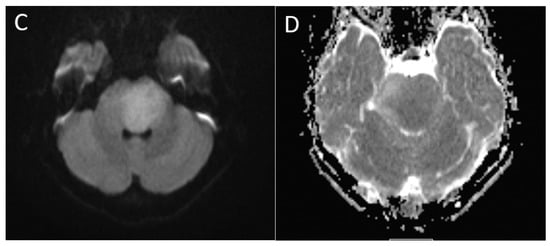

| Posterior fossa ependymoma | Fourth ventricle (PFB) or cerebellopontine angle (PFA) | Heterogeneous mass Calcifications common Intermediate diffusion (between medulloblastoma and pilocytic astrocytoma) Usually enhancing High myo-inositol on MRS |

| Pilocytic astrocytoma | Cerebellum (most common), brainstem, optic chiasm/hypothalamus | Most commonly, cyst with enhancing mural nodule although cystic component can be variable, and may be completely solid |